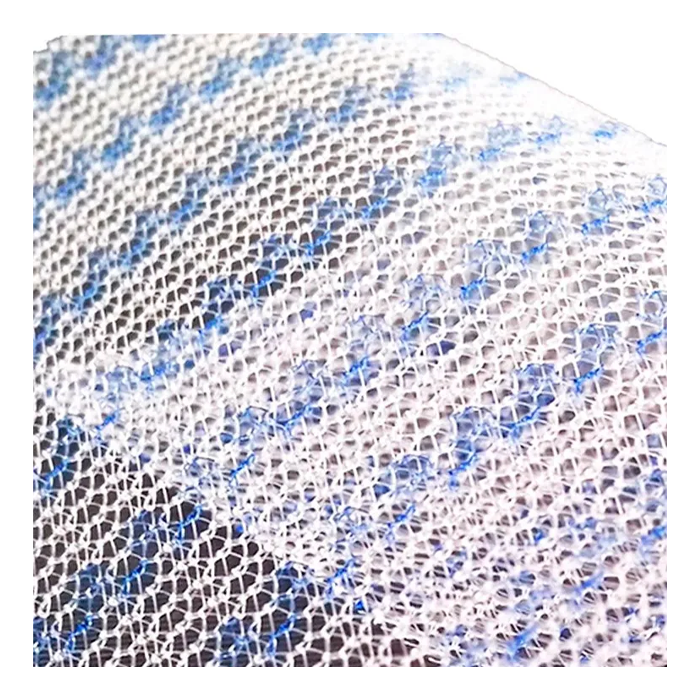

Эндопротез-сетка (сетка хирургическая) полипропиленовый для восстановительной хирургии ЭСФИЛ лёгкий, 15х10 см, Линтекс

Эндопротез-сетка полипропиленовая ЭСФИЛ лёгкий для восстановительной хирургии

Полипропиленовая хирургическая сетка ЭСФИЛ лёгкий от компании «Линтекс» — это современный высокотехнологичный имплантат, предназначенный для надежного и долговечного восстановления анатомических структур при пластических и реконструктивных операциях. Изделие специально разработано для хирургов, ценящих в работе баланс между прочностью, биосовместимостью и комфортом пациента в послеоперационном периоде.

Сетка ЭСФИЛ лёгкий представляет собой монофиламентное полипропиленовое полотно с облегченной структурой. Её ключевая особенность — оптимальное соотношение массы и прочности, что минимизирует реакцию тканей и способствует быстрой интеграции, обеспечивая при этом надежную механическую поддержку на весь срок службы.

- Облегченная структура. Сниженная плотность полимера и площадь контакта с тканями способствует формированию более мягкого и эластичного рубца, уменьшает ощущение инородного тела у пациента.

- Оптимальная пористость. Структура сетки способствует активному прорастанию соединительной ткани (фиброзной инкорпорации), что обеспечивает ее надежную фиксацию в организме и устойчивость к инфекциям.

| Тип структуры | Макропористая, облегченная (low-weight) |

| Поверхность | Не покрытая, макропористая |

Благодаря макропористой структуре, волокна сетки быстро прорастают соединительной тканью (коллагеновыми волокнами). Этот процесс, называемый инкорпорацией, прочно фиксирует имплантат, делая его частью анатомических структур.